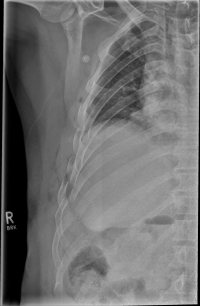

Rippenserie re                   Rippenserie re1